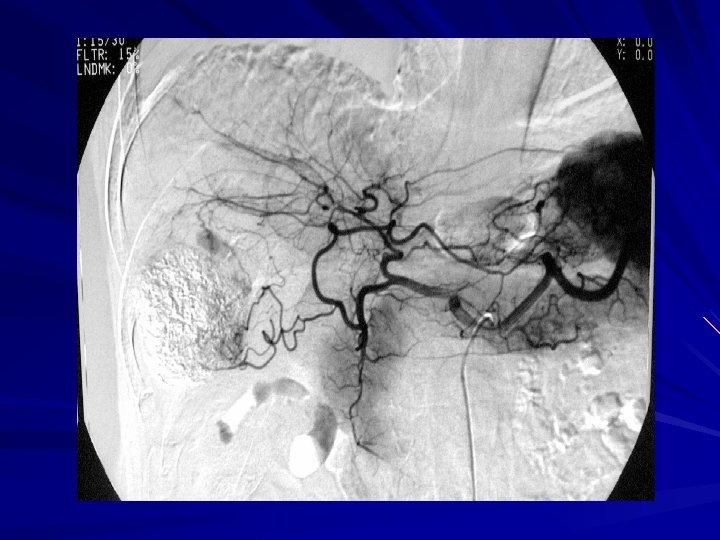

Use of micro-catheter— 2 nd TACE -----OA branches involved in blood supply-----

Use of microcatheter— OAs TACE

RESULT-3 16 patients had 2 or more repeated OA TACE 12 cases OAs occlusion, 4 cases of OA reperfusion, 3 cases were found new parasitic vessel from the nascent OA. OA parasitic blood supply of HCC lesions mainly was in the right and left medium lobe. 2 postoperative recurrence cases were found parasitic vessel from OA.

Discussion -3 3、 Superselective Intervention OA lumen small、 tortuous,their average diameter was only 23 mm,normal angiography usually was not obvious. When parasitic OA blood supply, the diameter may be significantly enlarged. Using the microcatheter will help improving the success of OA superselective catheterization. In this group of cases OA superselective catheterization success rate was 63. 9%. Reasons of superselective failure:OA was too fine;sharp angular between branch and the trunk;multi-cluster support OA was invaded so plexiform.